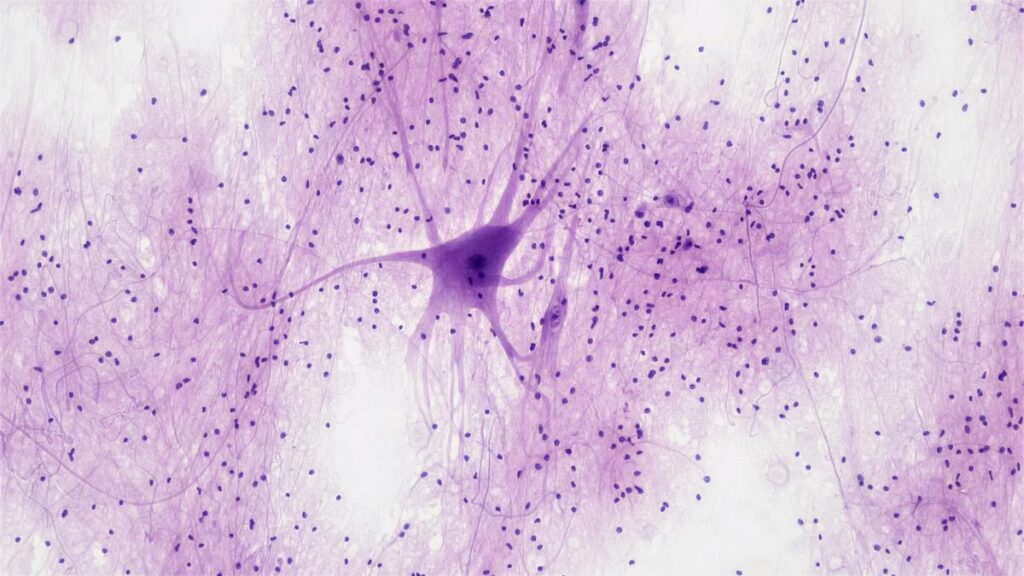

You were probably taught in high school that new neurons, or brain cells, are not born during adulthood. That it stops during your childhood. The actual picture has been more complicated: scientists have been debating among themselves for a long time as to when neurogenesis stops, although most of them believed it was possible in adulthood.A new study in Science now promises to kick this dust up all over again: it has reported evidence of neural progenitor cells and young neurons — which are the intermediate stages of cellular development — in the hippocampus, the memory centre of adult human brains.Promise and scrutiny“Historically, the brain was considered a non-regenerative organ,” Prem Tripathi, a senior scientist who studies neurogenesis at the CSIR-Indian Institute of Chemical Biology in Kolkata, said. “However, in 1998, a pioneering study provided the first direct evidence that new neurons could be generated in the hippocampus in adults, suggesting a regenerative potential in the adult brain.”This finding opened the door for exciting possibilities for regenerative therapies, particularly in ageing individuals suffering from neurodegenerative diseases like Alzheimer’s, Parkinson’s, and other dementias.The promise of regenerative therapies also brought more scientific scrutiny, however. The 1998 study had used brain samples of individuals suffering from brain cancers, prompting experts to question whether neurons in adulthood were being born due to the tumours.“The other criticism was that they showed this in a small sample size, only in five individuals,”, Navneet Vasistha, an assistant professor who studies neurogenesis at the University of Copenhagen, said.Even as doubt lingered over whether neurogenesis occurred in the human adult hippocampus, many research groups showed that neurogenesis did occur in the adult brains of mice, rats, and even monkeys.“Importantly, these studies identified several critical functions of adult-born neurons in the hippocampus,” Hiyaa Ghosh, associate professor of neurobiology at the National Centre for Biological Sciences, Bengaluru, said. This included “the ability to distinguish between very similar contexts, the ability to rewrite memories, and stress resilience.”These processes are all mediated by neural circuits in the dentate gyrus of the hippocampus, which is where new neurons are thought to be continually generated throughout life.Yet the evidence for adult neurogenesis in human brains has been inconsistent. One study from a group at the University of California in San Francisco found that while new neurons were born in the infant hippocampus, their numbers declined sharply within the first year of life. Another group replicated these findings independently, lending support to the idea that neurogenesis stops after infancy.At single-cell resolutionAmid this morass of conflicting studies, the new study — from researchers at the Karolinska Institutet in Stockholm — provides further evidence for adult neurogenesis using modern sequencing and machine-learning methods.The researchers isolated more than 4,00,000 neurons from the hippocampal region of post-mortem brain samples from (deceased) individuals aged less than a year to 78 years. Then they analysed them using a technique called single nuclei RNA sequencing, which provides a near-complete signature of genes that are expressed (or turned on) in each cell.This allowed the team to monitor hundreds of markers in cells simultaneously, including those specific to cells that divided regularly. They trained a machine-learning algorithm to recognise these markers using RNA sequencing data from hippocampal samples younger than five years old, when neurogenesis is well-documented to occur.“What we know from mouse models is that, typically, there are stem cells which every now and then get activated, proliferate to produce more intermediate progenitors, which also divide extensively,” Ionut Dumitru, one of the first authors of the study and a research specialist at Karolinska, said. “Those that survive become what we call neuroblasts — very young neurons.”In the study, the team was able to identify all three types of intermediate neuronal stages — neural stem cells, neural progenitors, and neuroblasts — using the machine learning algorithm even in adolescent and adult brain samples.“One of the key strengths of this study is in combining transcriptomics with spatial localisation,” Tripathi said.The authors also used advanced techniques called RNAscope and Xenium to doubly confirm that RNA signatures belonged to progenitor cells within the dentate gyrus.Ghosh added that “inclusion of a broad age range also strengthened their observations, demonstrating that neural progenitor cells can be detected throughout the human lifespan.”Both Tripathi and Ghosh also agreed that the RNA signature similarities between human and rodent progenitors supported the idea that adult neurogenesis is a conserved feature in mammals — meaning mammals don’t lose this ability in the course of evolution.Yet scepticism lingersNot everyone is convinced, of course.For example, Vasistha expressed concern that the authors relied on RNA signatures, which may not indicate functional relevance. According to the central dogma of molecular biology, DNA is transcribed into RNA, which is then translated into proteins, which finally perform cellular functions. So detecting RNA alone, Vasistha contended, doesn’t prove that a gene is actively producing a functional protein.“They could be remnants from the cell’s history, persisting in the cell or in the daughter cell,” he said.Instead, Vasistha continued, using antibody-based staining methods to label the marker proteins directly would have been more convincing. This is the same method that the two papers that couldn’t detect young neurons in the adult hippocampi used.While this method is often considered the gold standard to address whether a cell has a certain protein, it is also restrictive. Since the method is based on the ability to distinguish between fluorescent dyes, only four markers can be labelled simultaneously, as opposed to hundreds or more in the RNA sequencing method.Marta Paterlini, a researcher at the Karolinska Institutet and the other first author of this study, argued the same thing: that the team “wanted to move away from this restrictive antibody-based labelling method.”I tried so many different antibodies, but they all gave different results,” she added.This is to say: while the authors interpreted the variable antibody-based staining results as a limitation of the technique, others like Vasishtha remain cautious and question the identification and presence of neural progenitor cells.Another point of contention, with which Tripathi and Ghosh agreed as well, is that the number of neural progenitor cells is highly variable between individuals. The authors of the study attributed this to two reasons, technical and biological.“We never claimed our result to be quantitative,” Paterlini said. “We cannot tell exact numbers, but we can tell for sure that the neuroblast and neural progenitor cells are there in the adult hippocampus.”“Sometimes the techniques we use work well for some samples but not as well for others,” Dumitru added, highlighting the technical variability despite the team’s best efforts.The biological variation, they have further argued, stems from inherent genetic differences in the humans from whom the samples were obtained.“The human samples are so incredibly different from each other genetically,” he added, “in contrast, mouse models involve genetically similar individuals, which naturally reduces inter-individual variation.”This variation can also be attributed to environmental and lifestyle differences.“For example, physical activity increases neural progenitor cell proliferation, while chronic stress or social isolation reduces neurogenesis,” Ghosh said. “So two healthy individuals could show markedly different levels of neurogenesis based on such influences.”She also noted that including comprehensive metadata like stress levels, exercise habits, and psychological state could enrich future postmortem studies.A call for consensusAfter 27 years of intense debate and speculation, Dumitru and Paterlini are ready to move on.“Initially, sceptics would say ‘no neurogenesis, full stop’. But now, with new papers showing that there are progenitors, it’s shifted to ‘okay, there is neurogenesis, but very few neurons are born in adults, right?’” Dumitru said of the shifting trend.Vasistha remains unconvinced. He called upon the neurogenesis field as a whole to arrive at a consensus on the markers that scientists would have to use to identify neural progenitor cells, to standardise the protocols used for postmortem sample preparation, and to establish a robust validation framework based on RNA and protein detection for adult neurogenesis.All things considered, experts in the field agree the methodological differences seem to be the root cause of discrepancies across different studies.Adult neurogenesis is important in the hippocampus because it can explain how the hippocampus can perform critical memory-related functions. For example, some scientists have hypothesised that the dentate gyrus consists of a mixture of mature and immature neurons.“The hippocampal circuitry appears to rely on this unique property — maintaining a mixed population of highly excitable young neurons and sparsely firing mature neurons — to optimise processing,” Ghosh said.This dynamic composition in this region can account for plastic responses, i.e. flexibility in responses to similar situations, such as when you need to distinguish between where you parked the car yesterday versus where you parked today.From a clinical point of view, Vasistha said, “We currently don’t have any good therapies for dementia or for other kinds of cognitive impairment. So if somebody can uncover a mechanism by which you can boost the amount of neurogenesis, that would give people back some level of memory retention and cognitive ability, so they regain some dignity in their old age.”Dumitru added that “it is much easier, way more elegant, to encourage locally present neural progenitor cells to produce the neurons that are needed, rather than transplant externally differentiated stem cells, which can be an invasive and risky procedure.”However, these regenerative therapies are a long way away. Before clinical applications can be designed, many fundamental questions persist.For the group from Karolinska, the first step is to understand more about the adult-born neurons like their function, number, and distribution.“To kill the debate, we must show the specifics,” Dumitru added.The team is also examining other areas in the adult brain where neurogenesis may occur, which could launch yet another spirited debate.Sheetal Potdar has a PhD in neuroscience and works as a science writer.